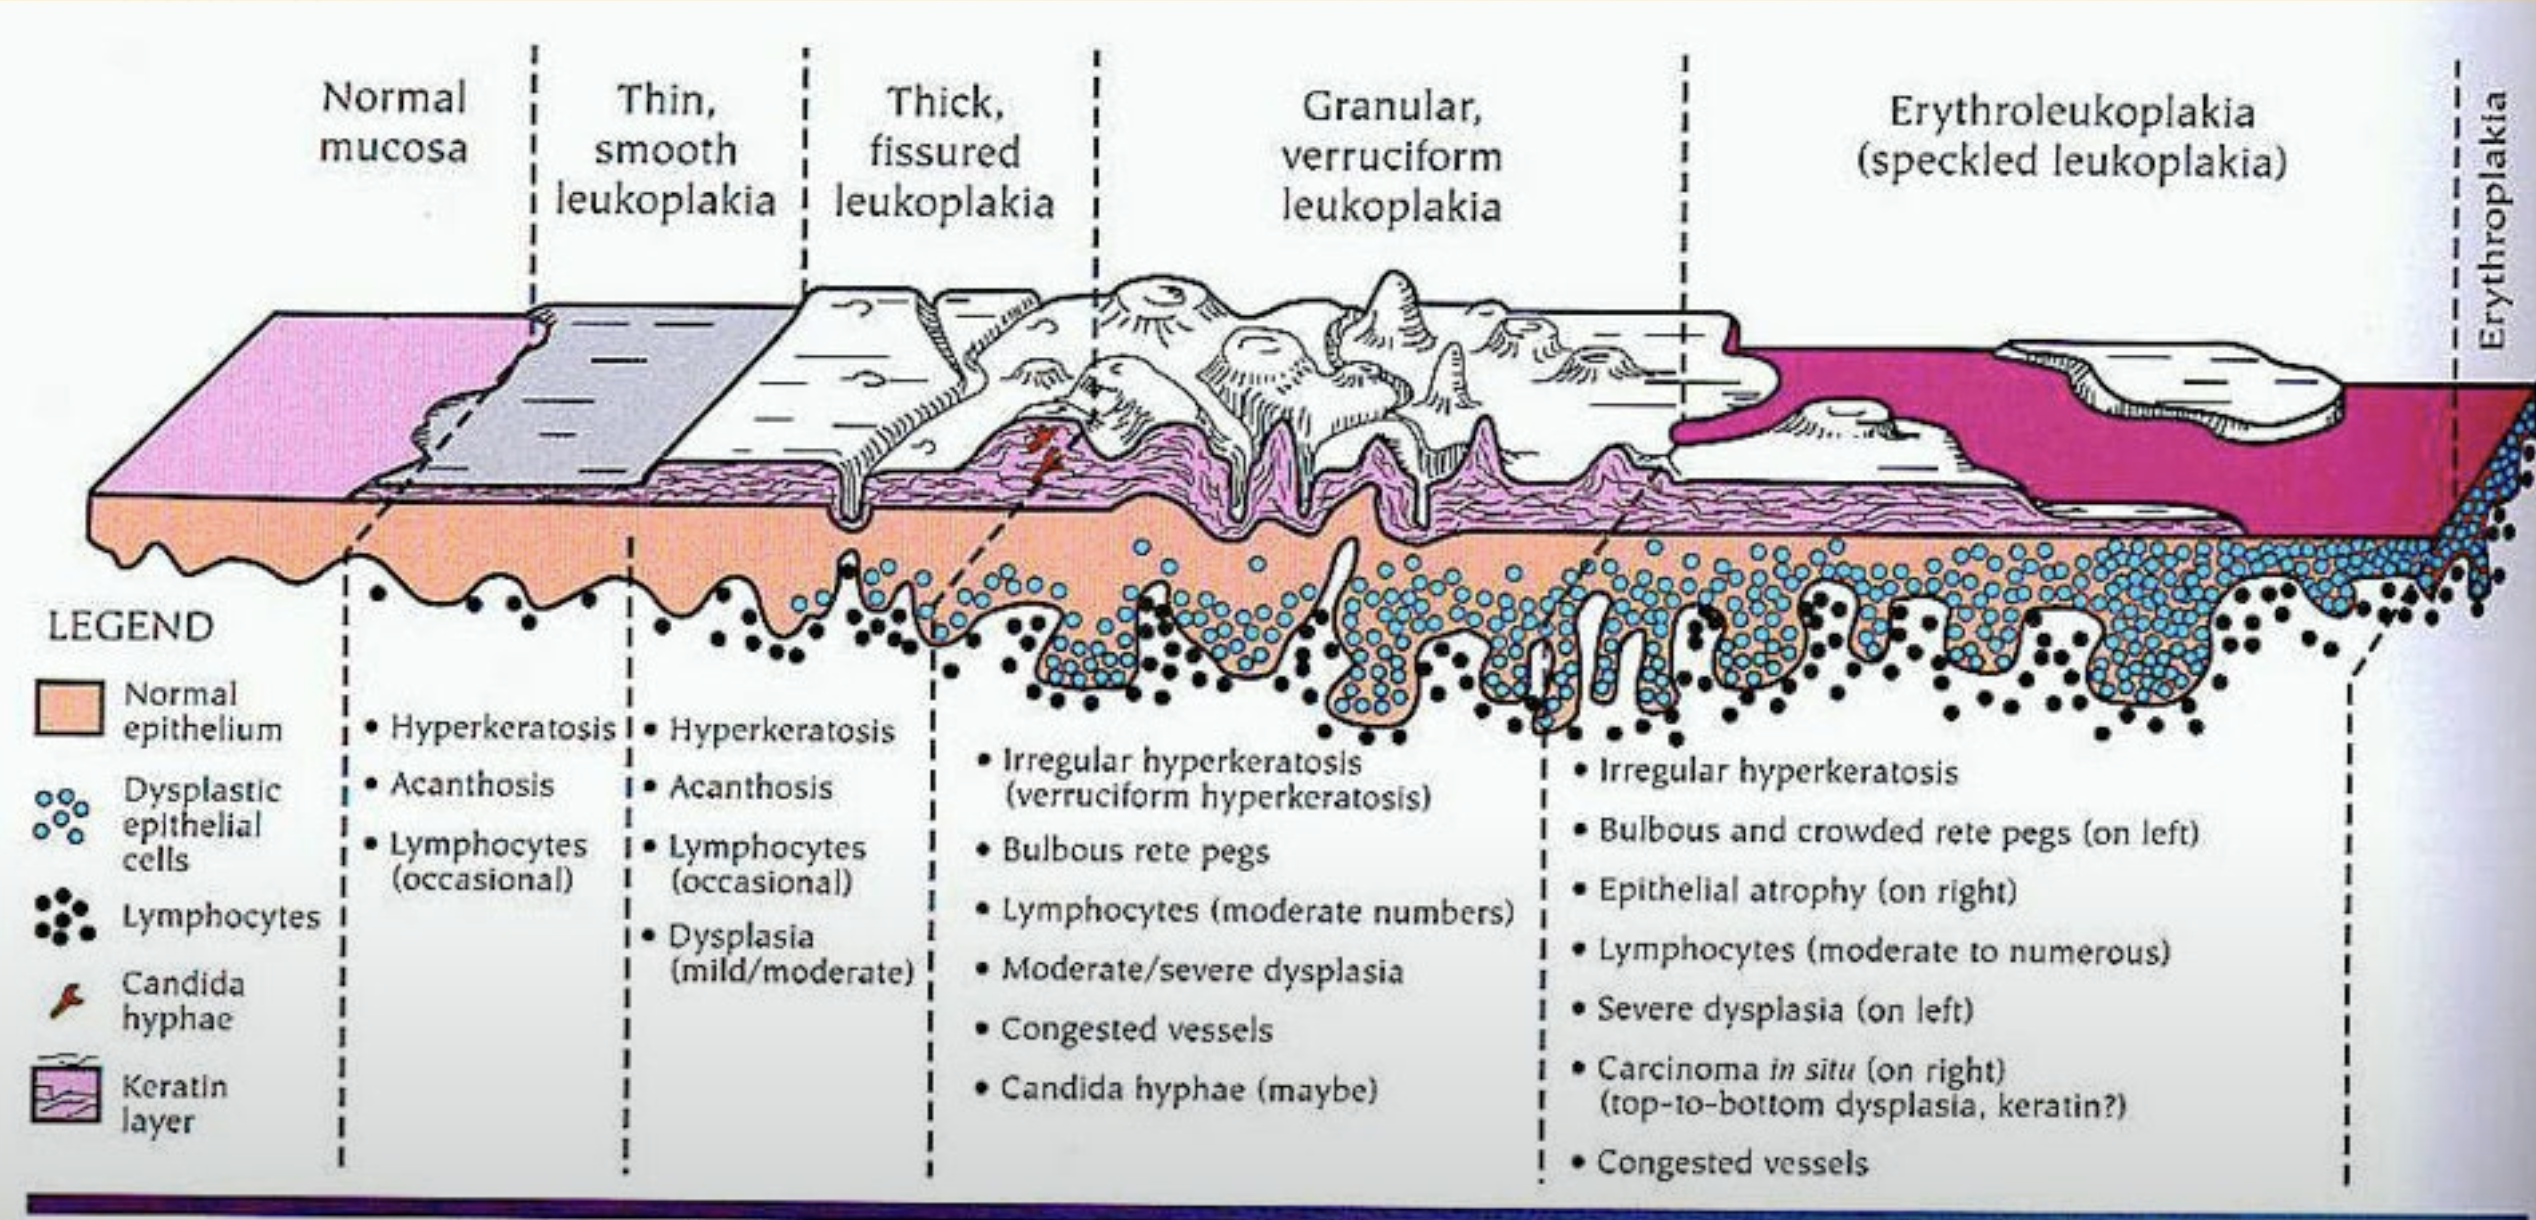

Oral potentially malignant disorders (OPMD)

| Leukoplakia, Erythroplakia | 紅斑較嚴重,不產生角質  |

|

||

. |

||||

| Poliferative verrucous leukoplakia (pbl) | ? |

|

||

|

||||

Oral epithelial dysplasia (OED)

OED ∈ OMPD

- 硬顎較少發生。

- 分為三個程度

Mild

- 影響到下三分之一

- Basal cell 增生,變大

- Rete ridge 變寬

- 底層 keratin (紅染)

- 可能發炎

Moderate

- 到中三分之一

Sever